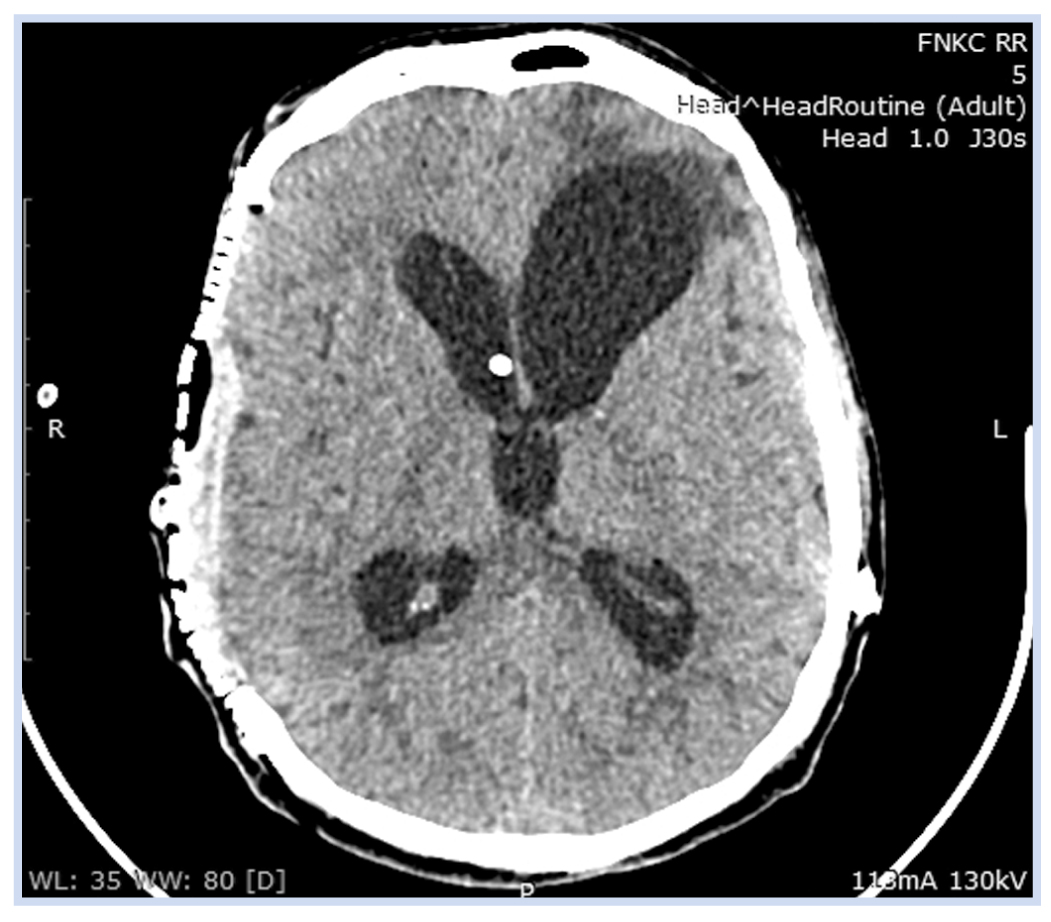

На КТ головы от 31.03.2020: линейный перелом лобной кости справа. Справа определяется постоперационный дефект на уровне лобной, теменной и височной костей размером ~107 × 93 мм, на этом же уровне отмечается западение вещества головного мозга в дефект, максимально до ~30 мм. Вентрикулярный катетер шунта в левом боковом желудочке. Постоперационные изменения в правой гемисфере, латеральная дислокация головного мозга влево до 17,5 мм на уровне прозрачной перегородки. Очаг измененной плотности на границе лобной и теменной долей правой гемисферы следует дифференцировать между гематомой в поздней подострой стадии и постоперационными изменениями. Сглаженность борозд, вероятнее всего, обусловлена последствиями изменения внутричерепного давления, нельзя исключить проявление отека вещества головного мозга левой гемисферы (рис. 3).

Рис. 3. Пациент К., 50 лет, с посттравматической гидроцефалией и посттрепанационным дефектом костей свода черепа: компьютерная томограмма головы от 31.03.2020

Примечание. Определяются гигантский посттрепанационный дефект костей свода черепа справа, значительное западение вещества мозга в дефект, смещение срединных структур влево, удовлетворительное положение вентрикулярного катетера вентрикуло-перитонеального шунта в области отверстия Монро справа, узкий правый боковой желудочек.